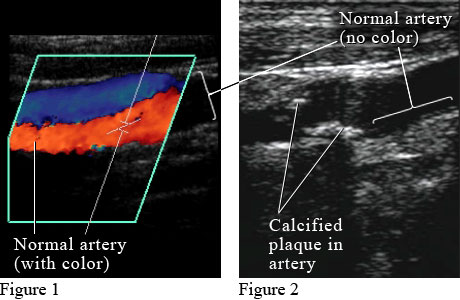

Figure 1 shows a colour Doppler ultrasound picture of blood flowing through a normal artery (red) and vein (blue). Figure 2 shows an ultrasound picture of an artery narrowed by the buildup of calcium and fat (cholesterol) in the inner lining of the artery, called plaque, which leads to "hardening of the arteries" (atherosclerosis).